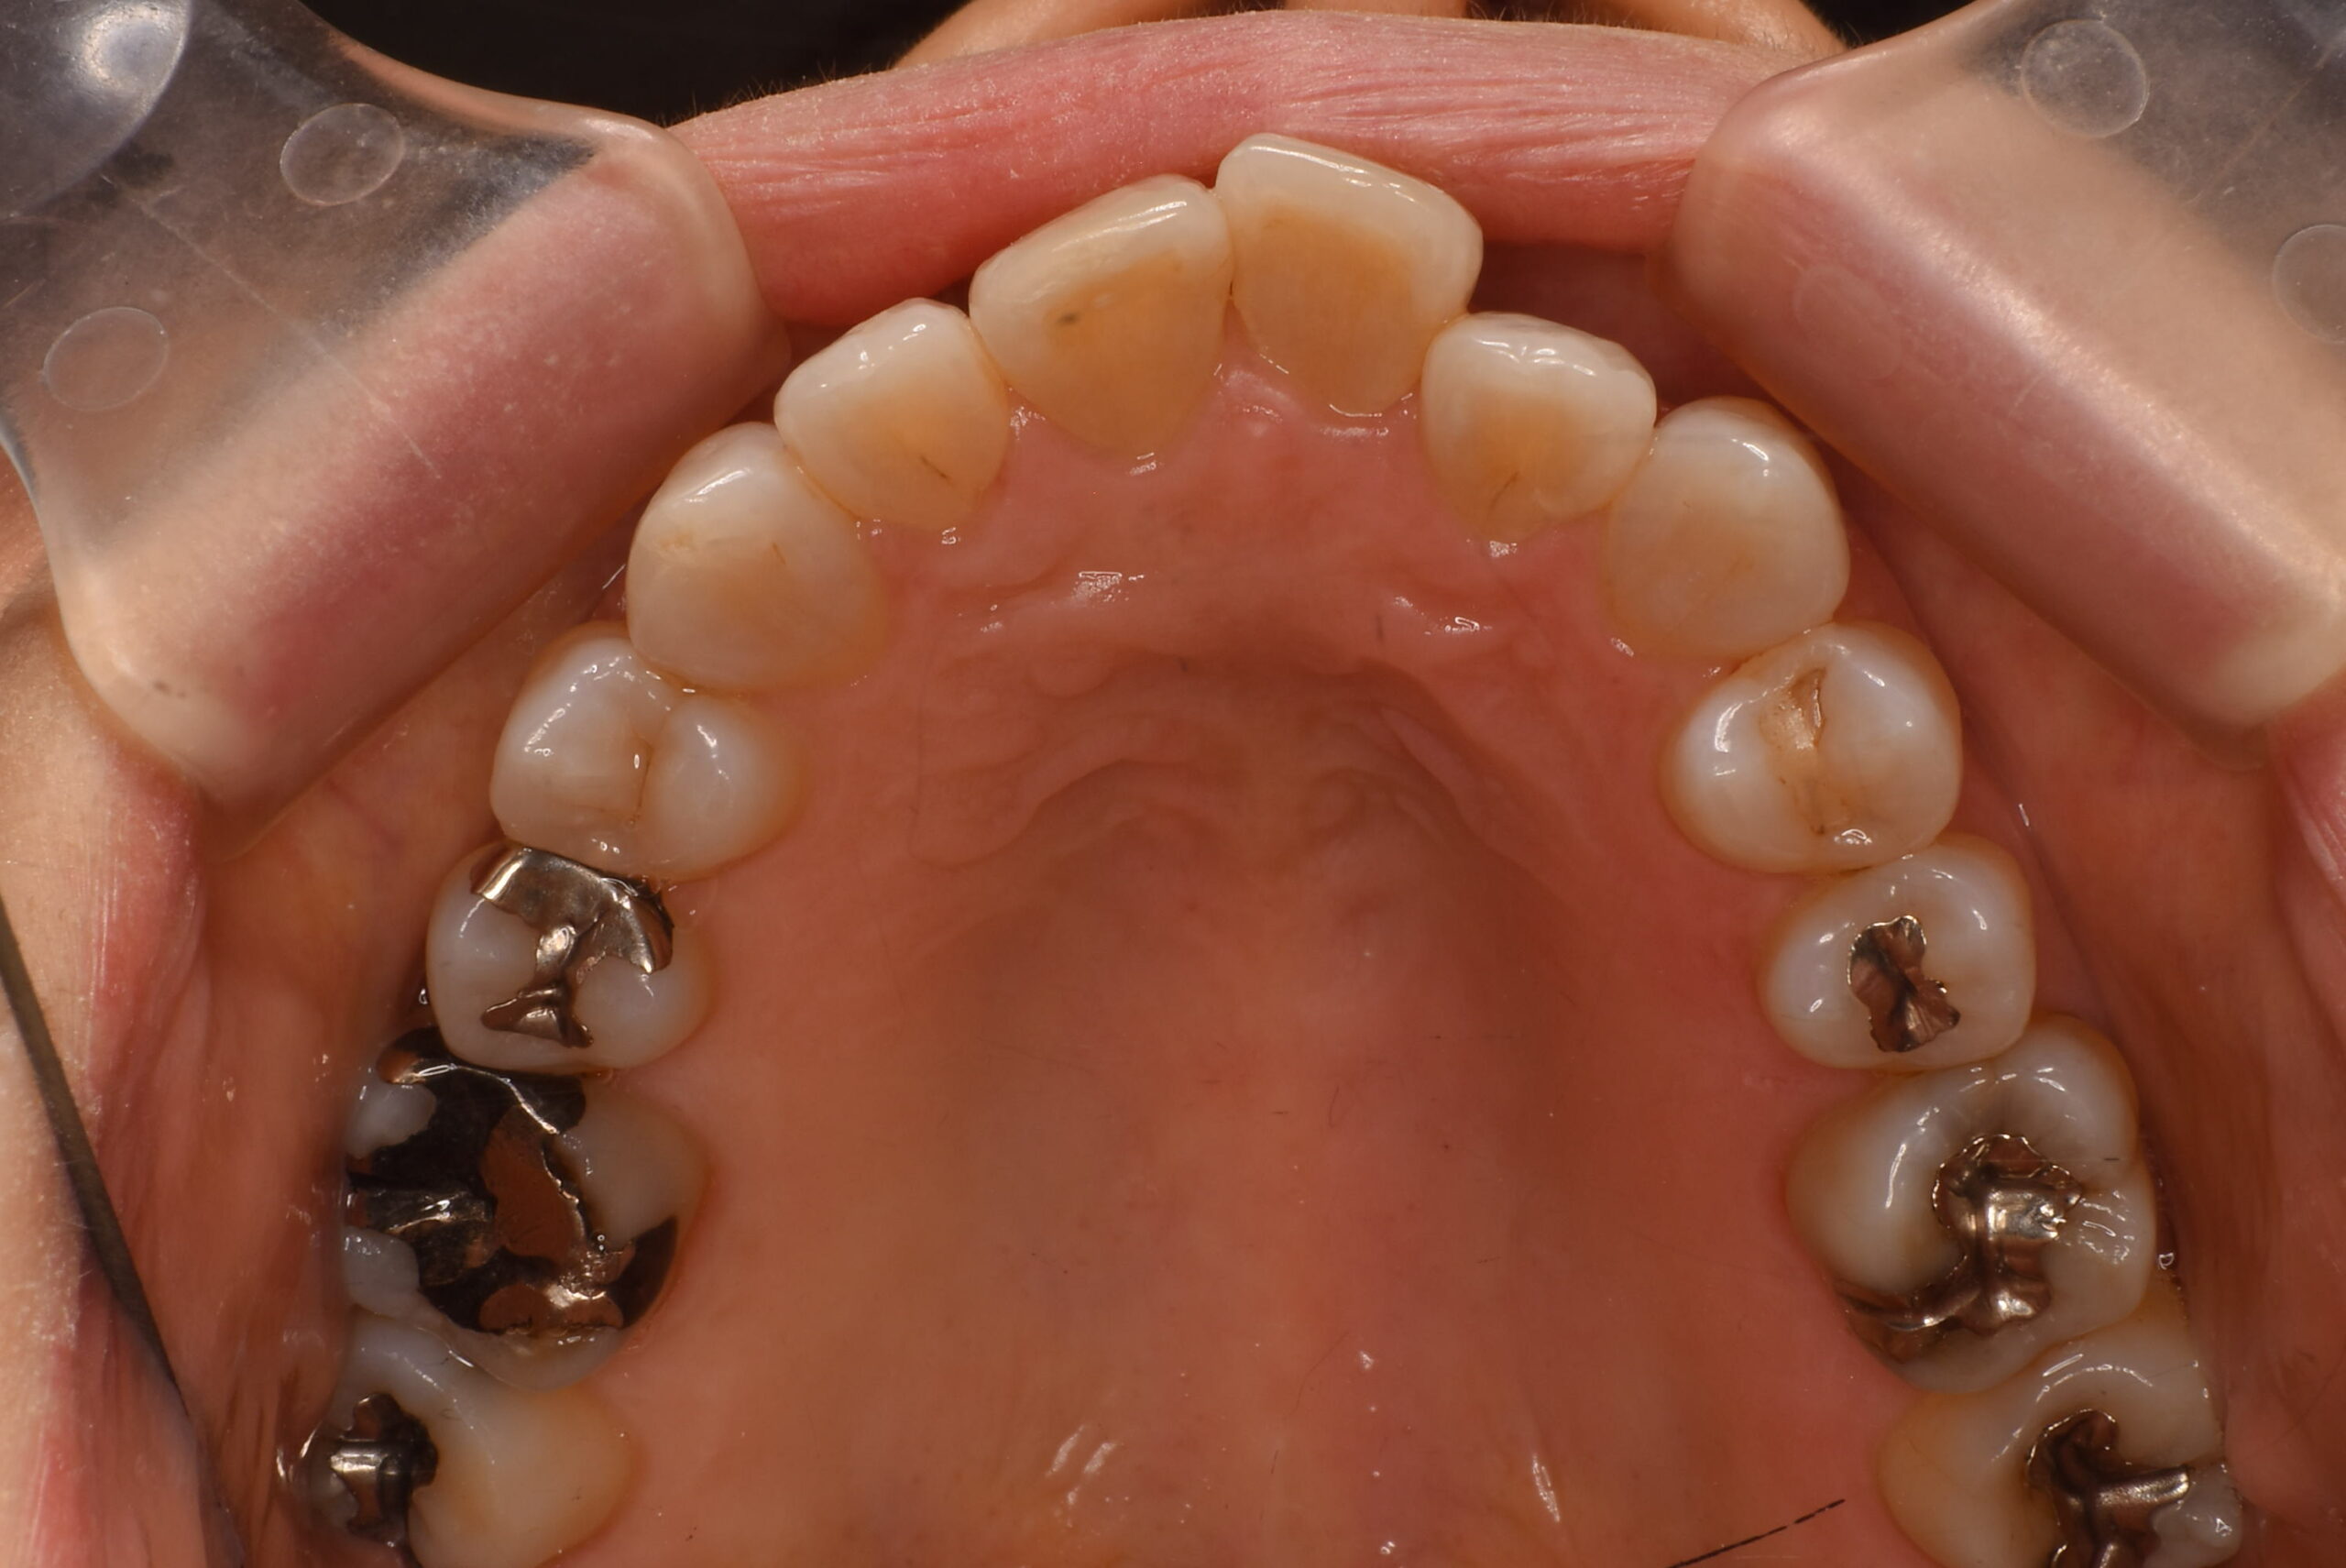

- BEFORE

上顎咬合面_治療前

| 治療内容 | 患者様は、不揃いな歯並びと噛み合わせの違和感、加えて将来的な口腔内の病気への不安を訴えて来院された。また、慢性的な肩こりや首の痛みもあり、これらが歯並びや咬合との関連についても心配されていた。 インビザラインによるマウスピース型矯正を選択。アライナーを用いて歯列全体を整列し、叢生の改善とともに前歯部の位置と角度を理想的な状態に調整。必要に応じて歯と歯の間のわずかな削合を行い、歯を並べるスペースを確保した。 |